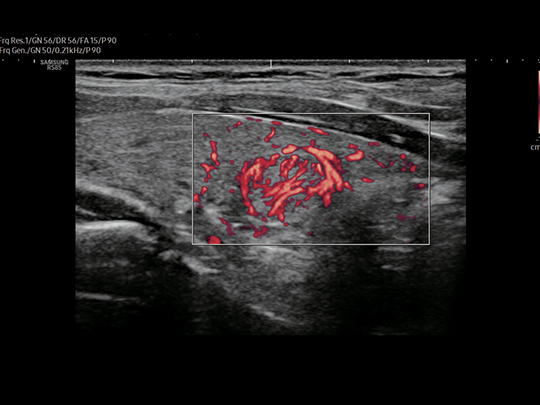

LA2-14A

- Small parts, vascular, musculoskeletal, abdomen